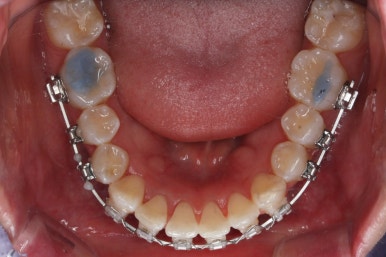

틈은 다 다물어졌고, 부가적인 정교한 마무리 과정을 더 거치게 됩니다.

중앙선도 잘 맞고 교합도 잘 마무리되었습니다.

이 뽑은 자리가 다시 벌어지지 않게 앞니가 다시 틀어지지 않게 유지철사를 부착하고 마무리를 하였습니다.

중앙선, 교합, 뻐드러짐 모두 좋아졌고 이를 뽑고 교정했지만 발치 공간이 남지 않고 잘 마무리 되었습니다.